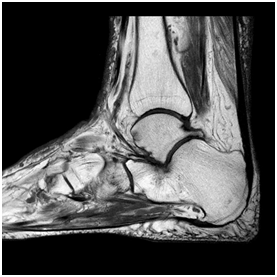

A 66 year old man with seropositive rheumatoid arthritis was diagnosed in 2009. His co-morbidities included emphysema, atrial fibrillation (on warfarin), and chronic haematuria. His medications included etanercept and methotrexate 20mg. This patient had right ankle pain for 5 years, but it was worse in December 2013, so an XR was taken which appeared normal. An ultrasound guided intra-articular steroid injection was performed in February 2014. This did not alleviate the pain, so a MRI was requested. It which showed non-displaced insufficiency fractures of the cuboid and talar neck, which appeared to be healing. There was also pes planus with lateral hind foot talocalcaneal impingement. He was reviewed by orthopaedics and supplied with a Jura-boot with medial arch support (Figure 7-10) (Table 2).

Figure 8 Case 2 MRI sagittal view right ankle. Old healing talar neck fracture.

Figure 9 Case 2 MRI coronal view right ankle. Talocalcaneal impingement.

Figure 10 Case 2 MRI sagital view right ankle. New non-displaced lateral cuboid fracture.